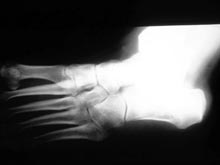

Пластик, полученный из кукурузного крахмала и соединения из вулканического пепла, может изменить жизни пациентов с ортопедическими травмами, которые нуждаются в замене кости, передает NDTV. Итак, речь идет о биоразлагаемом полимере, усиленном наночастицами монтмориллонита (глинистый материал). Материал рассасывается в теле за 18 месяцев. Когда материал полностью растворится, на тот момент уже новая кость сформирована.

Чтобы создать этот материал, ученым пришлось впрыскивать диоксид углерода в смесь полимера и глины. В итоге получился имплантат, похожий на пену, но твердый как кость. Пористостью обладает и натуральная костная ткань. Схожесть искусственного материала с натуральным обеспечивает хорошую приживаемость и высокую скорость образования новой костной ткани.

Ученые создавали новый материал с прицелом на то, чтобы использовать его без укрепляющих элементов. С обычными же имплантатами требуется установить дополнительные элементы, так как сами имплантаты недостаточно прочные. А эти укрепляющие элементы повышают риск инфекций. Если их нет, то предполагаемый исход лечения изначально лучше.